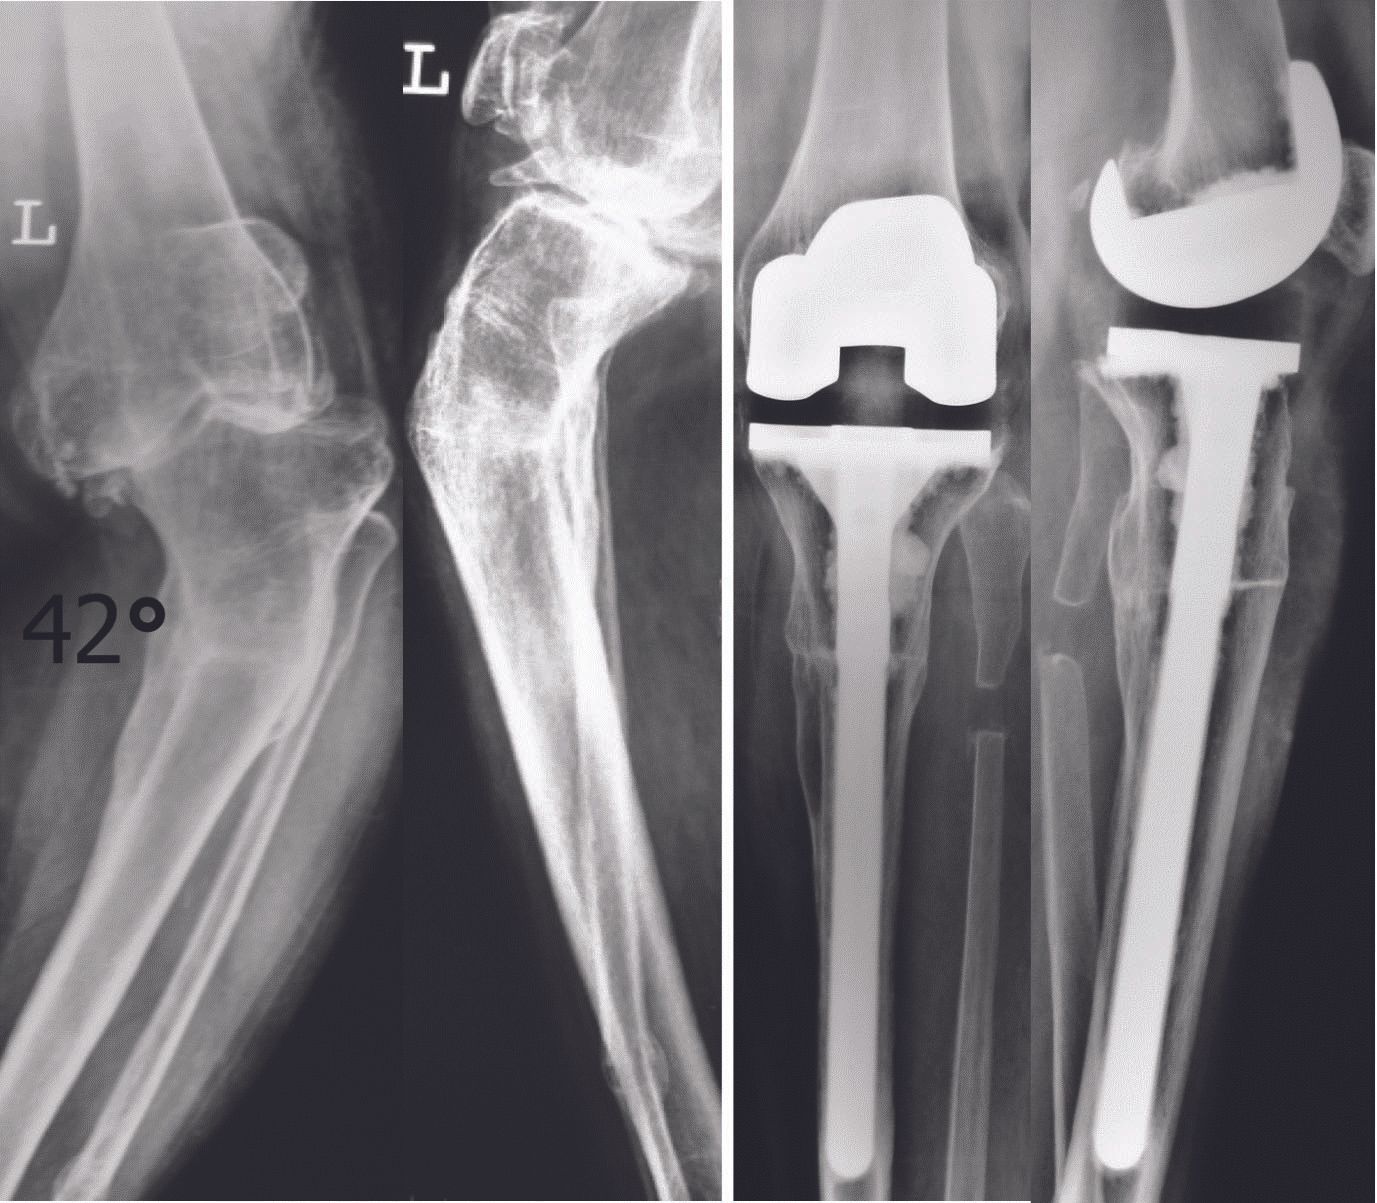

The author has performed over 12000 total knee replacements, over 6000 with computer navigation and has made several observations which are published in scientific studies 1-12. Here is the method followed which has satisfactorily achieved alignment and balance without requiring release of the superficial medial collateral ligament2 and without using constrained implants (only posterior cruciate substituting designs have been used in almost all cases)(Fig 1).

5. Flexion of the knee relaxes the posterior soft tissues and excludes them from contributing to medio-lateral imbalance

12. Mullaji AB, Padmanabhan V, Jindal G. Total Knee Arthroplasty for Profound Varus Deformity: Technique and radiological results in 173 knees with varus more than 20 degrees. J Arthroplasty 2005; 20(5): 550-561